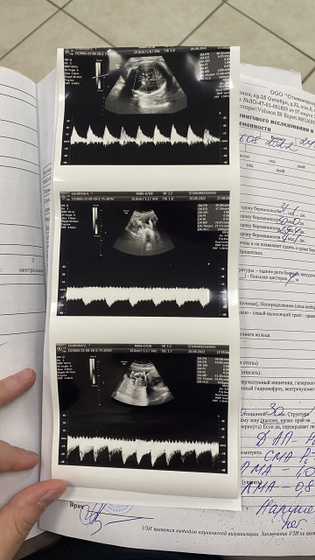

Но во время узи когда лежала на спине была тахикардия и у меня и у ребёнка до 170 подскакивал пульс.

Но узист меня вертела на боках и вроде норм было до 158 снижалось.

Нарушений кровотоков не поставила.

Но сделала много снимков кровотоков.

Когда лежала на спине и на боках

Как она сказала это передавливает эту Вену полую.

И поэтому скачет чсс

А так все хорошо. Малышка развивается хорошо. Гсд не влиятельна неё. Диета помогает. Вес 1500. Все по сроку